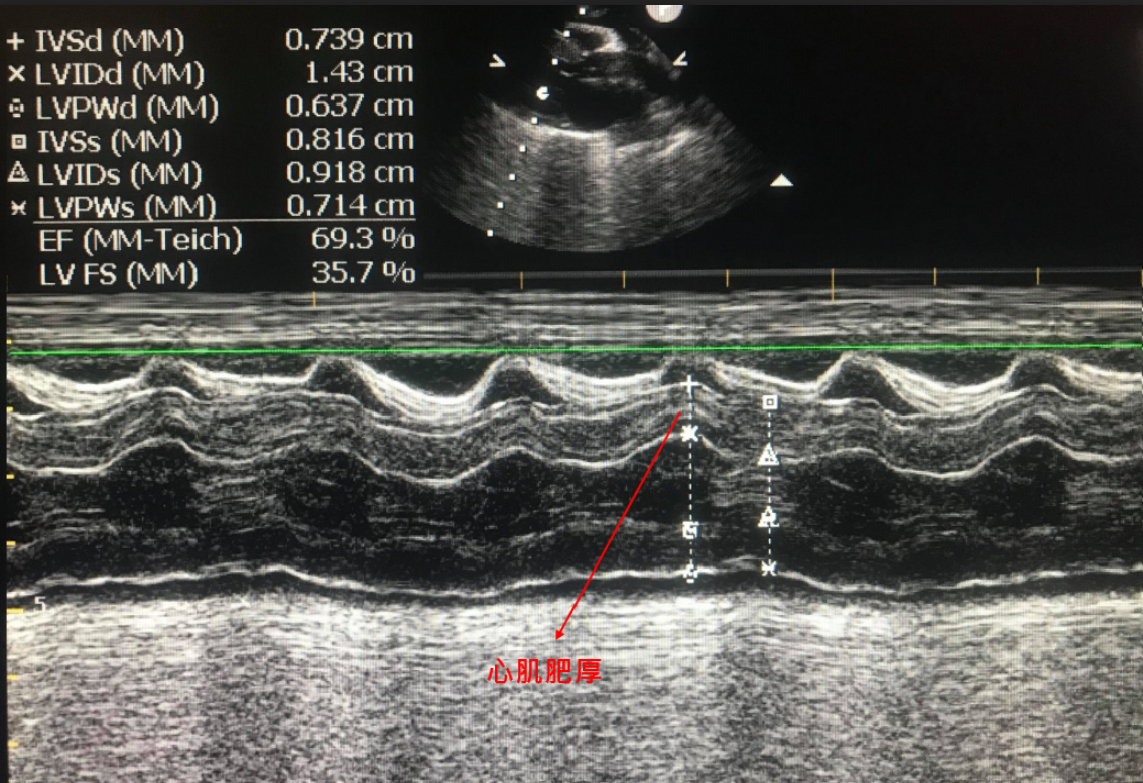

貓咪的心臟病

更多